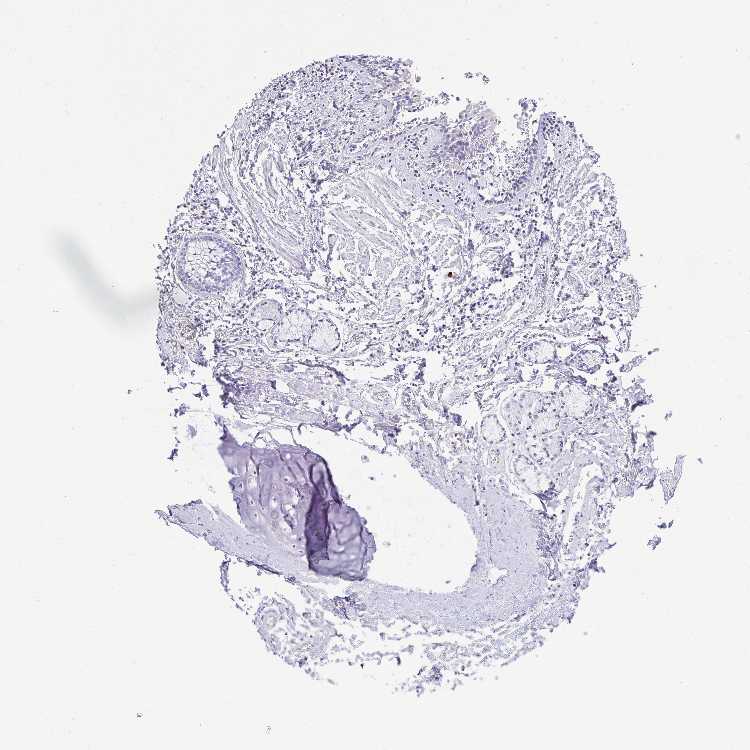

TISSUE PRIMARY DATA SOFT TISSUE Show tissue menu

SOFT TISSUE 1 - Antibody stainingi

Antibody staining in the annotated cell types in the current human tissue is reported as not detected, low, medium, or high, based on conventional immunohistochemistry profiling in selected tissues. This score is based on the combination of the staining intensity and fraction of stained cells.

Each image is clickable and will lead to virtual microscopy that enables deeper exploration of all samples and also displays staining intensity scores, fraction scores and subcellular localization as well as patient and tissue information for each sample.

Antibody HPA007649Antibody HPA052474Antibody HPA052484Antibody CAB037174

Peripheral nerve ---Low

SOFT TISSUE 2 - Antibody stainingi

Peripheral nerve LowNot detectedNot detected-